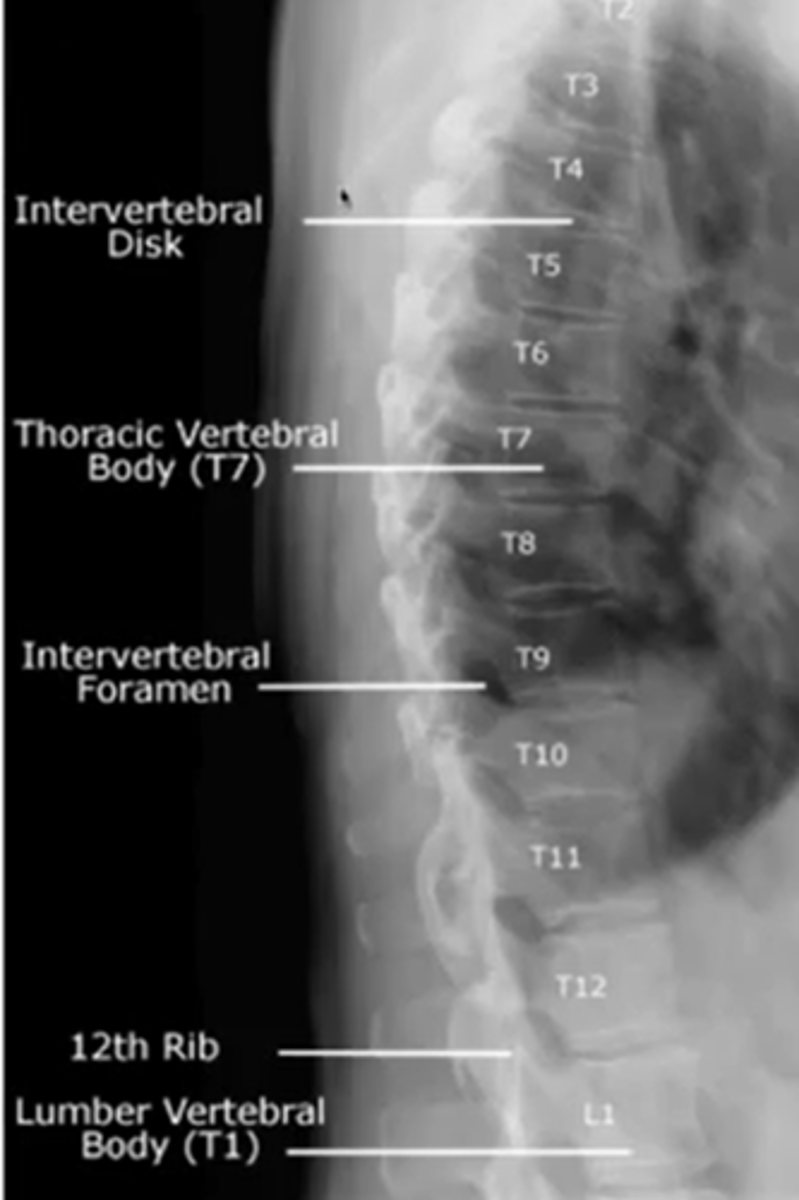

when looking at the thoracic spine

what view should you choose to see

vertebral bodies

lateral

intervertebral disc height

intervertebral foramina

what are the three lines for the thoracic spine